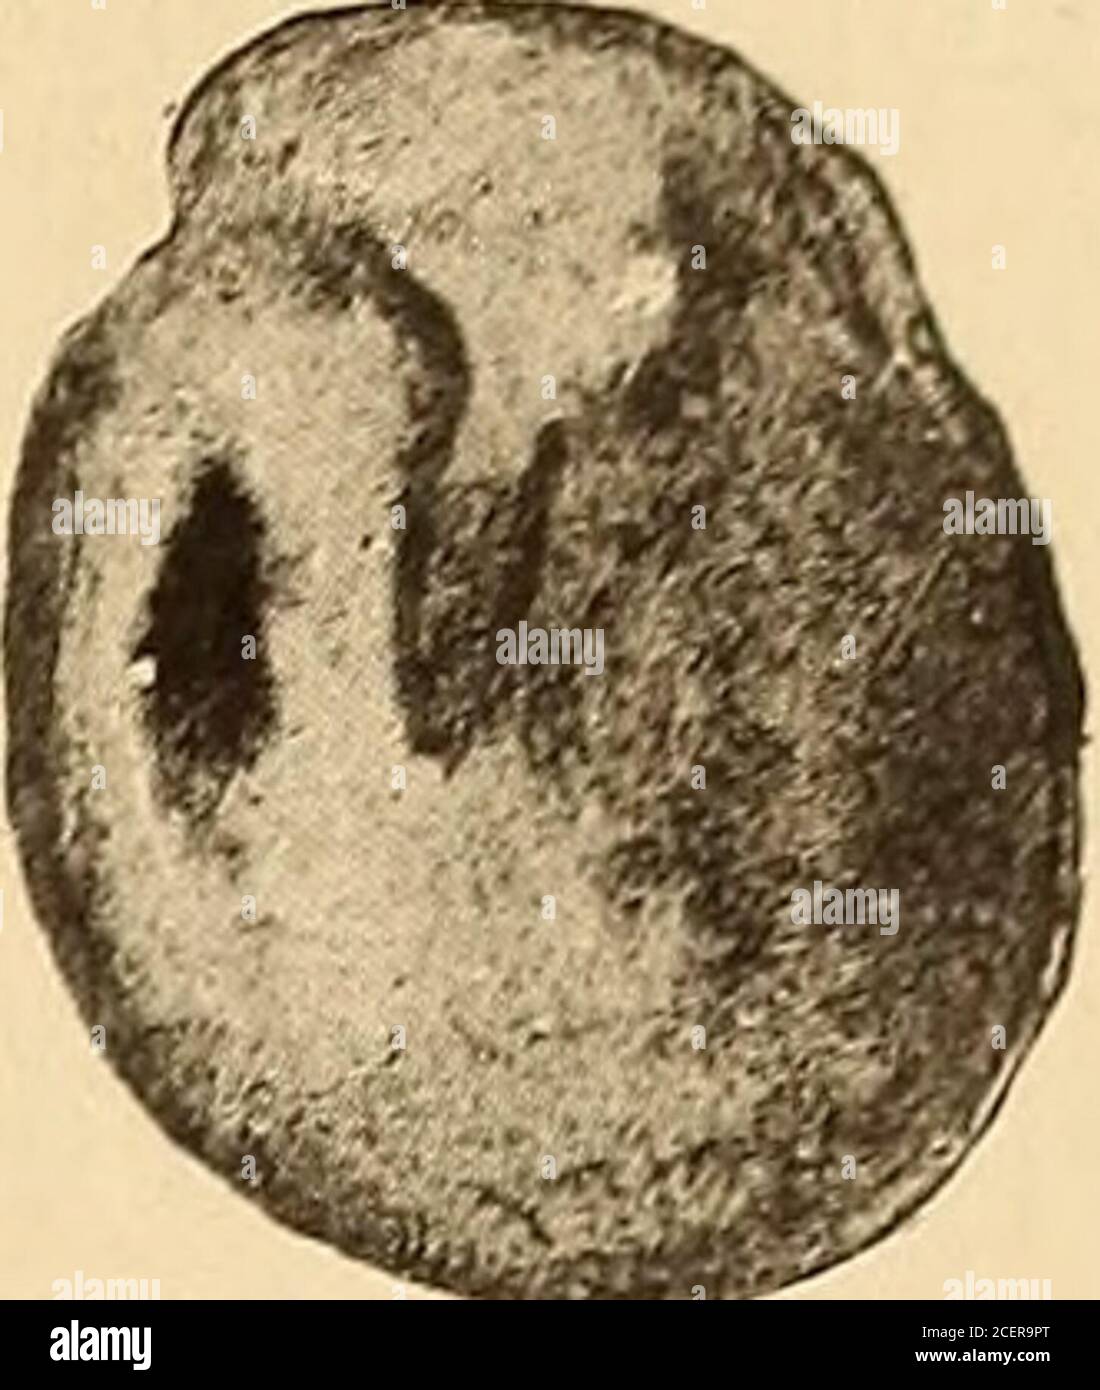

Normal Landmarks Of Tympanic Membrane . Several key anatomical landmarks can be identified on the surface of the tympanic membrane, particularly during an otoscopic. The membrane should be translucent and smooth, with no evidence of inflammation, fluid, or perforation. A normal tympanic membrane exam generally shows a pearly gray color with landmarks clearly visible, such as the cone of light, light reflex, umbo, and pars tensa. A distinctly red, yellow, or cloudy tympanic membrane. Moderate to severe bulging of the tympanic membrane, with loss of normal. Steps of the otoscope exam include. It is composed of three layers: For a normal tympanic membrane, you should be able to observe*: Clinicians perform an otoscope exam to assess the condition of the external auditory canal (eac), tympanic membrane (tm), and the middle ear.